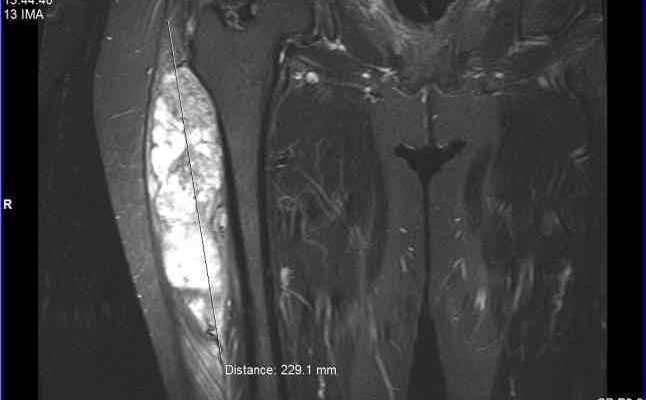

Ранняя диагностика сарком мягких тканей и их дифференциация Саркомы мягких тканей ─ это группа редких, но агрессивных опухолей, которые могут развиваться